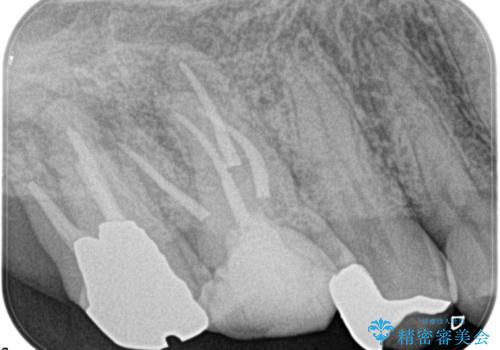

湾曲根管。精密根管治療

検査の結果、右上第一大臼歯の診断を、歯髄壊死とし抜髄を行っております。

湾曲根管に対してエラーなく処置を行えております。